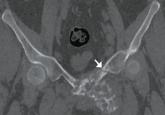

ArticleBrown tumor of the pelvis Author:Ayoub Nahal, MDPublish date: December 1, 2015Hyperparathyroidism increases the number and activity of osteoclasts, causing lytic lesions.Read More